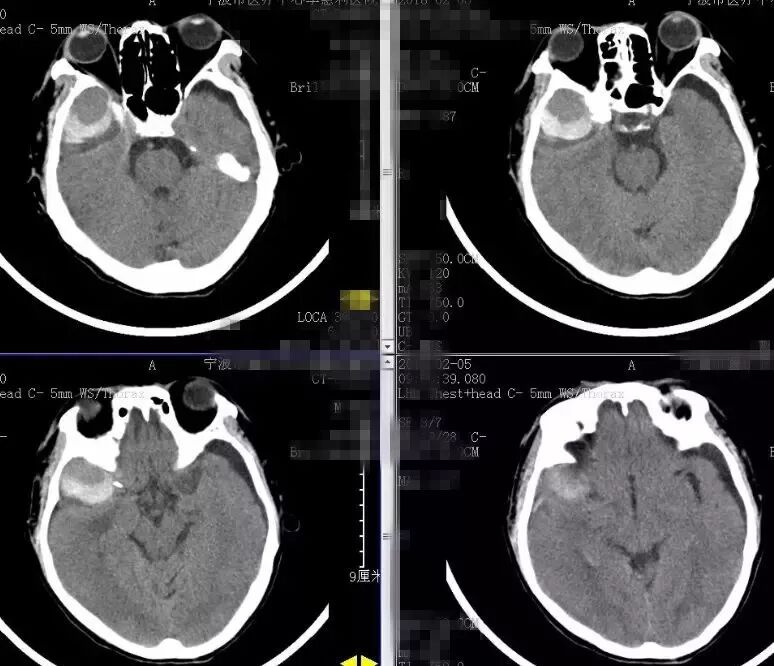

辅助检查:2018-1-10复查头部及胸部CT:右颞部硬膜外血肿。右侧颞骨、颧弓骨折,右侧颅底多发骨折(图1)。右侧液气胸,胸腔引流管在位。右侧多发肋骨骨折。右肱骨正侧位片:右侧肱骨下端粉碎性骨折。

图1. 2018-1-10入院时头CT:右颞部硬膜外大血肿。右侧颞骨、颧弓骨折,右侧颅底多发骨折。

鉴于患者有轻微头痛头晕,病情稳定,颅高压尚可,入院后完善各项辅助检查,预防感染、止血、神经营养等保守治疗。拟头部情况稳定后,转骨科行右肱骨手术治疗。保守治疗一周后(2018-1-17)头颅CT显示右颞硬膜外血肿基本同前(图2),遂继续保守治疗。2018-1-22及27日再次复查头颅CT,显示右颞硬膜外血肿较前逐渐吸收,密度降低(图3)。

患者头痛头晕逐渐好转,右眼视力也较前好转。胸腔积血明显减少,拔除引流管。遂转骨科行右肱骨手术治疗。骨科手术后患者病情恢复可,也无明显头痛加重等。出院前常规给予复查头颅CT(2018-2-5)提示右颞部硬膜外血肿新鲜出血(图4)。考虑暂缓出院,并转回李惠利医院神经外科。患者转回神经外科后当天出现剧烈头痛,再行复查头颅CT及预约CTA。2018-2-9 CT提示右颞硬膜外血肿较前明显增多(图5)。

图2. 2018-1-17头颅CT显示右颞硬膜外血肿基本同前,密度稍降低。

图3. 2018-1-22及2018-1-27再次复查头颅CT显示右颞硬膜外血肿较前逐渐吸收,密度降低。

图4. 骨科术后复查头颅CT(2018-2-5)提示右颞部硬膜外血肿新鲜出血。

图5. 2018-2-9 CT提示右颞硬膜外血肿较前明显增多。